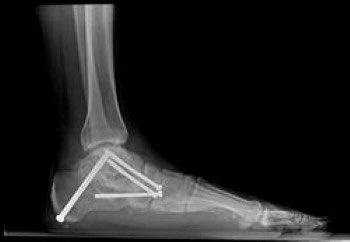

📍عند فشل العلاج التحفظي في تحسين آلام المريض، يتم اللجوء إلى الحل الجراحي 🔪، و الذي قد يشمل:

- إطالة الأوتار أو نقلها من مكان لأخر.

- قص و تعديل العظام.

- تثبيت مفاصل القدم في حالات متقدمة.